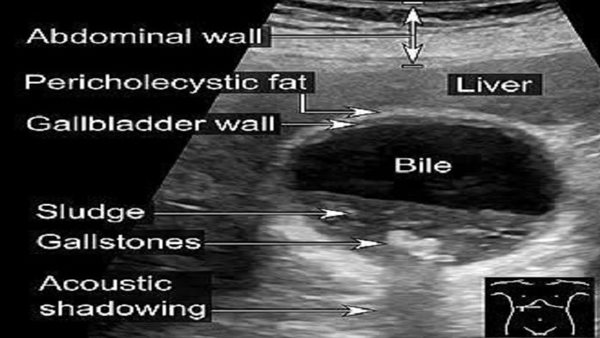

أسباب الإلتهاب المراري الحصوي الحاد.. يشهد الوسط الطبي في الآونة الأخيرة ارتفاعًا ملحوظًا في معدلات الإصابة بـ" الالتهاب المراري الحصوي الحاد"، وهي حالة مرضية ترتبط بتكون الحصوات داخل المرارة وتسبب التهابات حادة قد تؤدي إلى مضاعفات خطيرة تهدد حياة المريض، فهيا نتعرف خلال السطور التالية على أسباب الإلتهاب المراري الحصوي الحاد.

وعن أسباب الإلتهاب المراري الحصوي الحاد، أوضح الدكتور محمد إسماعيل، أخصائي أمراض الباطنة والصدر، أن هناك ارتفاعًا غير معتاد في عدد حالات التهاب المرارة، وكذلك في عمليات استئصالها، منذ أواخر نوفمبر الماضي، موضحًا أن هذه الزيادة أثارت قلقًا واسعًا بين الأطباء في مختلف التخصصات.

ينتج انسداد القنوات المرارية عن الحصوات الصغيرة الأقل من 6 ملم، وتظهر أعراضه في: